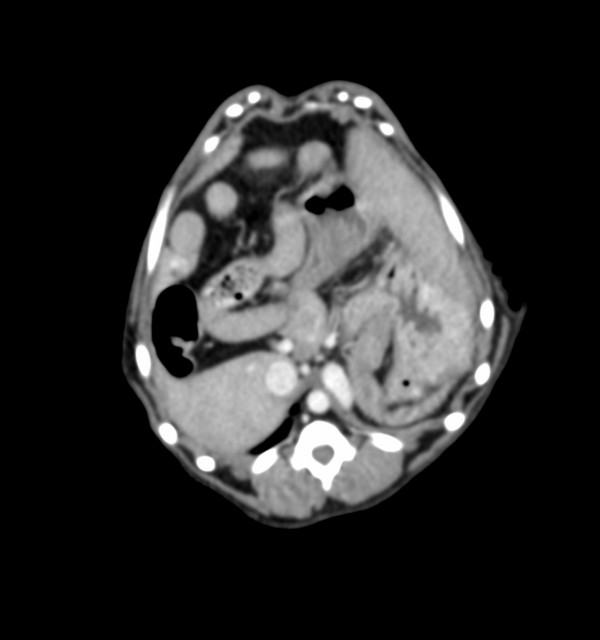

門脈体循環シャントを疑い、CT検査を実施。

CT検査の結果、門脈体循環シャント(脾静脈-横隔静脈シャント)と診断。

門脈体循環シャントの診断にはCT検査が非常に有用である。